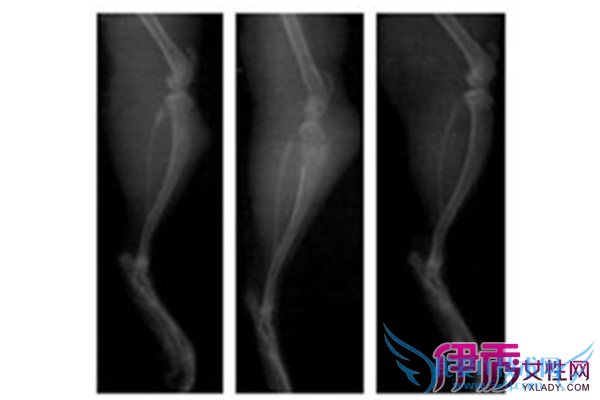

4)畸形 由于肿瘤的存在,可引致发育不对称,或压及骺板,可引发畸形。

6)病理骨折 由于肿瘤存在及其破坏作用,易致病理骨折。如巨细胞瘤每无症状,常在发生病理骨折才被发现。

(3)畸形 由于生长年龄、部位、肿瘤性质等因素,可引发畸形。如多发性软骨瘤,影响生长,可质肢体弯曲、不等长。内生软骨瘤因膨胀可使手足小骨畸形。肿瘤侵及骺板亦可引起发育异常。